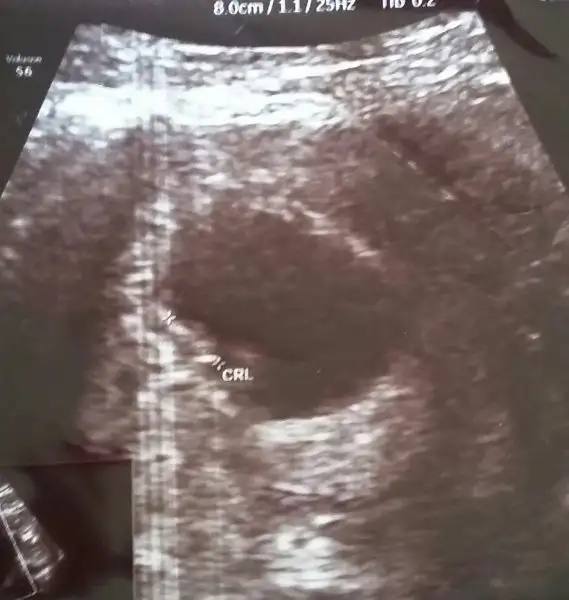

benim minigimede bakarmisiniz? karindan usg

Kizlar 3 resim attım 6 haftalik karindan usg bana da yorum yapin nolur.

kızlar bende resim attım 2 adet bakabilir misiniz ? karından usg 6+1 günlük tahmin için erken mi acaba